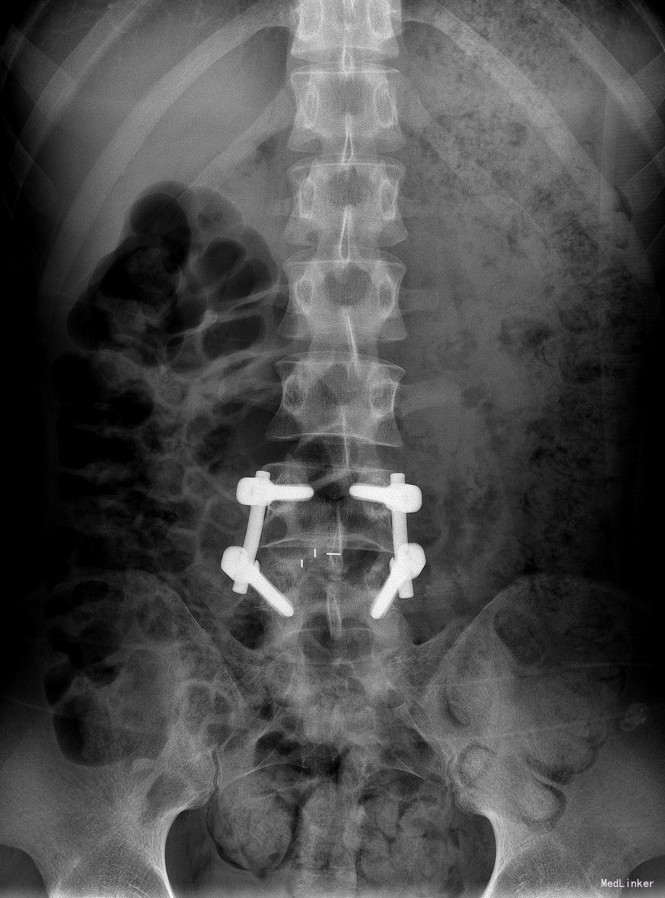

腰椎椎管内占位 腰椎后路开窗减压+椎间融合+内固定术

双下肢疼痛消失,生活自理